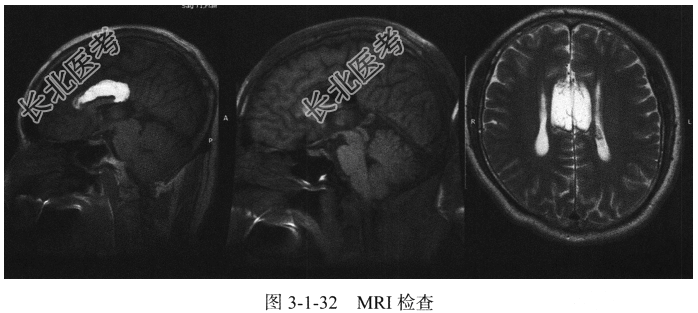

- [材料题] 患者,男,49岁,无明显症状(图3-1-32)。

- 简答题1、患者可能诊断为什么?

- 简答题2、该患者MRI检查有何异常改变?